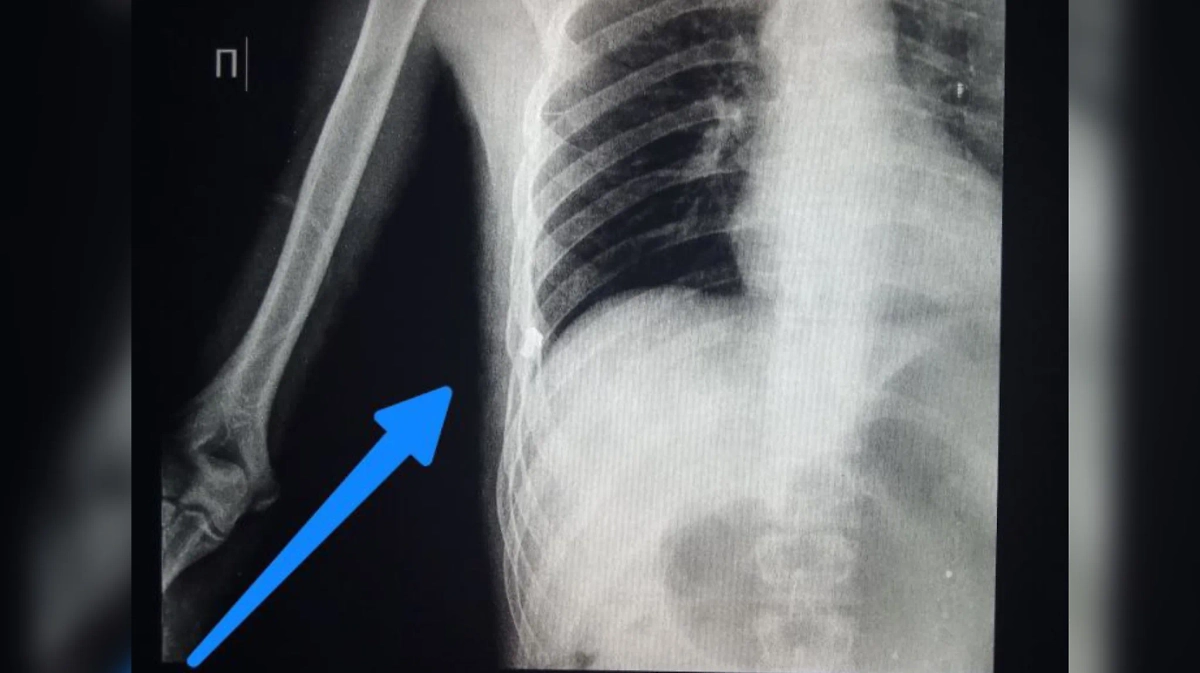

ВСУ стали использовать болты в качестве поражающих элементов. Фото © Telegram /КУЧИЦ Мед . KUCHITS MED

Вооружённые силы Украины в условиях дефицита вооружений начали делать самодельные бомбы с "начинкой" из винтиков и болтов. Об этом рассказал российский хирург группы медицинского отряда спецназначения Сергей Кучиц.

"Противник начал чаще применять самодельные взрывные устройства, где в качестве поражающих элементов использует винтики и болтики! Переход от националистической идеологии к методам и оружию террористов проходит весьма наглядно", — написал врач и приложил рентгеновские снимки российских военных, на которых видны поражающие элементы.